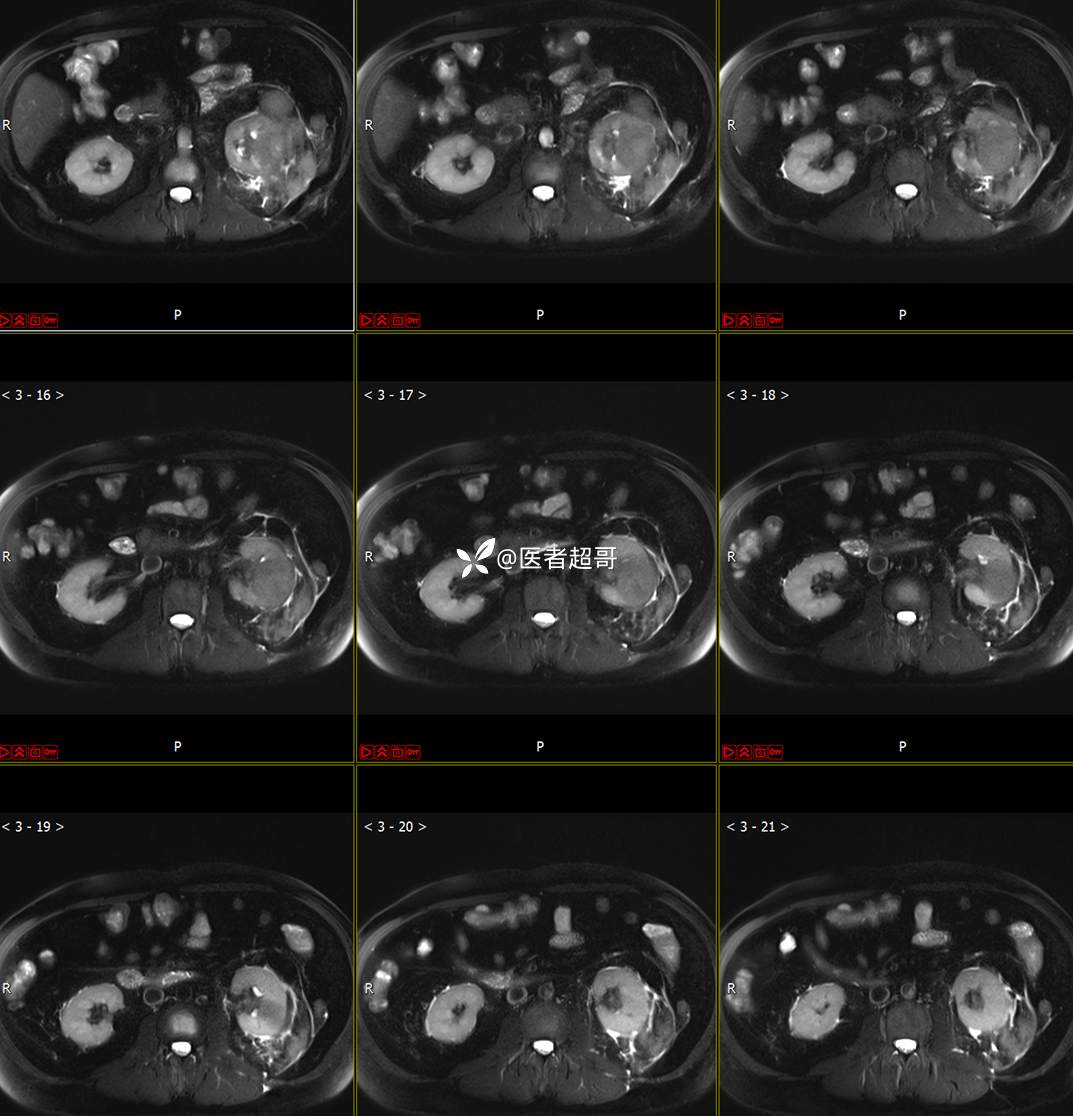

主 诉:查体发现左肾肿物9天。

现病史:患者9天前于附属医院行常规腹部CT检查时,发现左肾占位性病变并肾周脂间隙软组织增多,自述无明显腰腹部不适,无尿频、尿急、尿痛及肉眼血尿,未予特殊治疗,患者近期无头晕头迷,胸闷气急,腹胀腹泻及其他部位明显不适,遂至我院就诊,门诊以“肾肿物”收入院,患者自发病以来,精神可,睡眠饮食可,大便正常,体重无明显减轻。